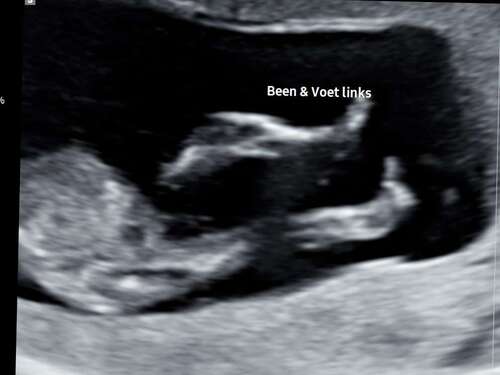

Aangezien de vorige gesloten is, bij deze nog een keer de foto. Met precies 12 weken! Ben benieuwd 😊

Het is een foto van de benen.. maar zal er tussenin ook iets te zien zijn? ...

Lijkt vrij hoog te zitten dan. Ik zou eerder denken aan de navelstreng🤭

Ik zie alleen een hele overduidelijke nub goed hoor dus bestudeer ze niet zo lang en goed met bewerken enzo als nubster🤭

Wat ik wel doe is dat ik kijk naar nub én skull theorie. Daarmee samen kom ik bij jou uit op een meisje💗

Je laatste foto is dan weer wat verwarrend, maar dat kan ook de navelstreng zijn aangezien we de hoek niet goed kunnen zien waarin de foto genomen is🙃